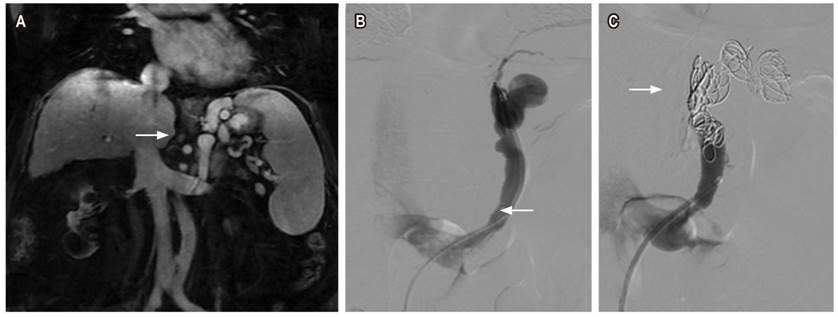

Tercer caso

Paciente femenina de 66 años con antecedente de cirrosis biliar primaria e hipertensión portal, quien consulta por dos episodios de hematemesis. En la EVDA se encontraron 4 cordones varicosos dilatados en el tercio distal del esófago, que ocupan el 25 % de la luz esofágica, sin signos rojos, ni estigmas de sangrado agudo reciente o antiguo. En el lago gástrico, se encontraron restos hemáticos antiguos. No se encontró evidencia de sangrado activo, y a nivel subcardial hacia la curvatura mayor se encontró una várice grande sin estigmas de sangrado agudo, reciente o antiguo. Se realiza una resonancia magnética de abdomen en la que se encuentran várices tortuosas adyacentes a la curvatura menor del estómago y shunt gastrorrenal (Figura 3A); debido a estos hallazgos, se considera que la paciente tiene un riesgo alto de resangrado, por lo que se considera que requiere embolización. Se realiza una venografía selectiva opacificando la várice tortuosa en una curvatura menor, shunt gastrorrenal (Figura 3B) y embolización con coils (Figura 3C) ocluyendo el flujo en várices. Este procedimiento fue realizado sin complicaciones y se dio alta temprana a la paciente.